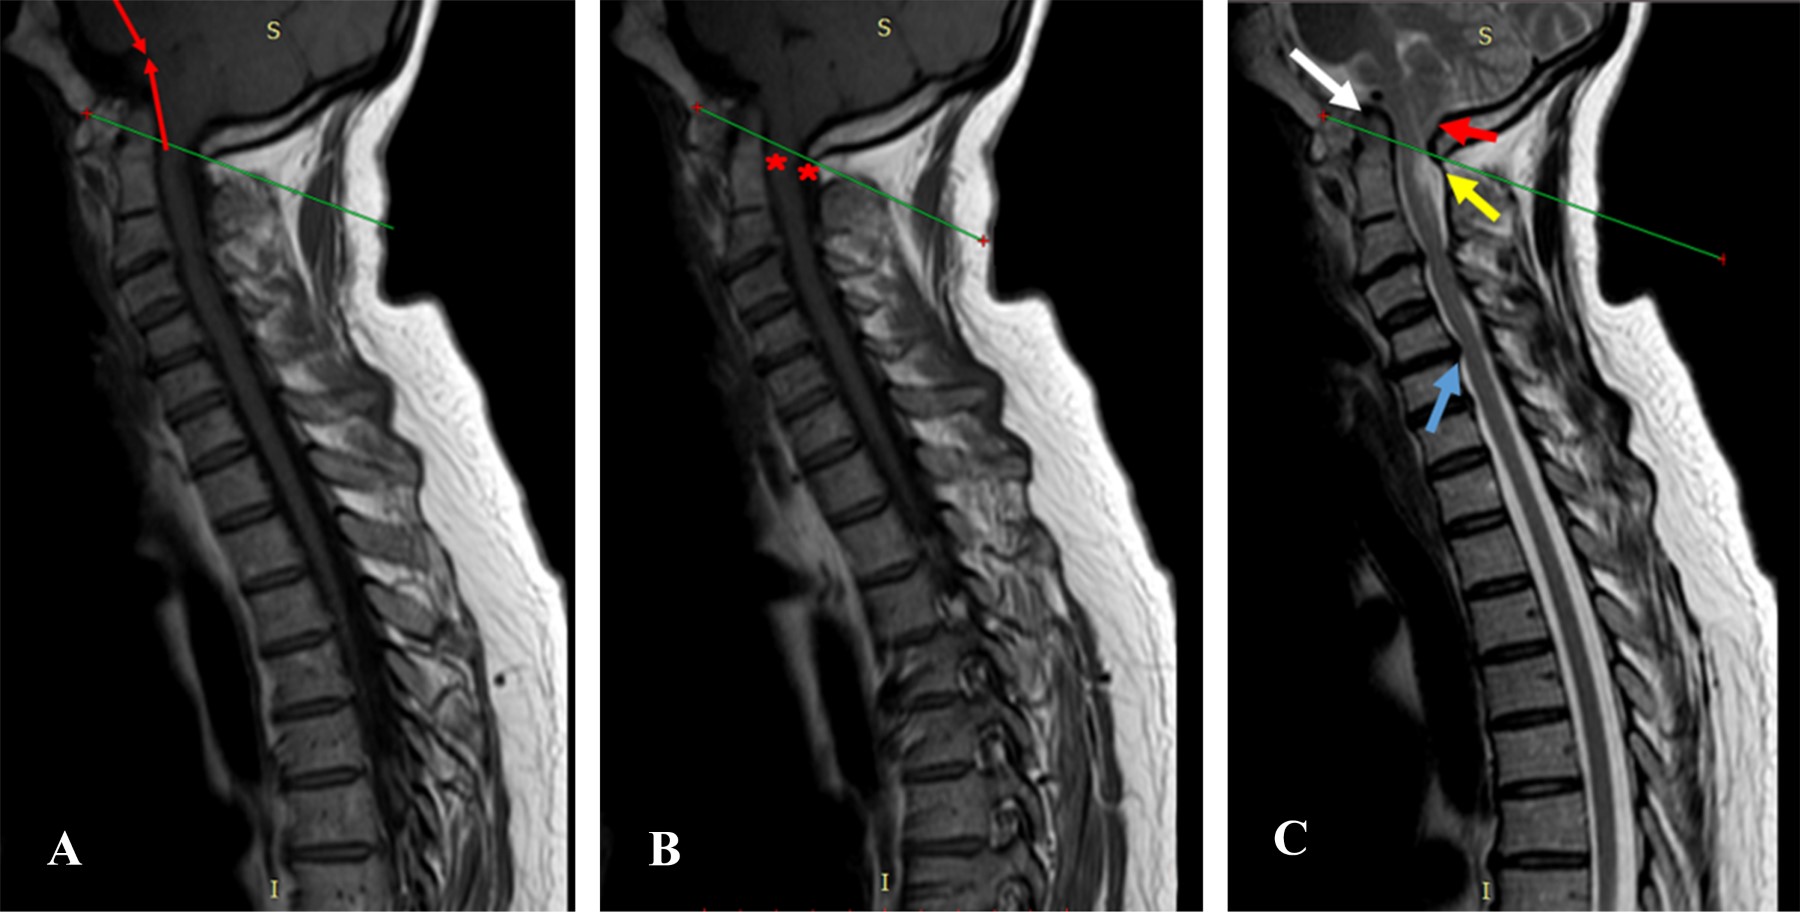

Figure 1